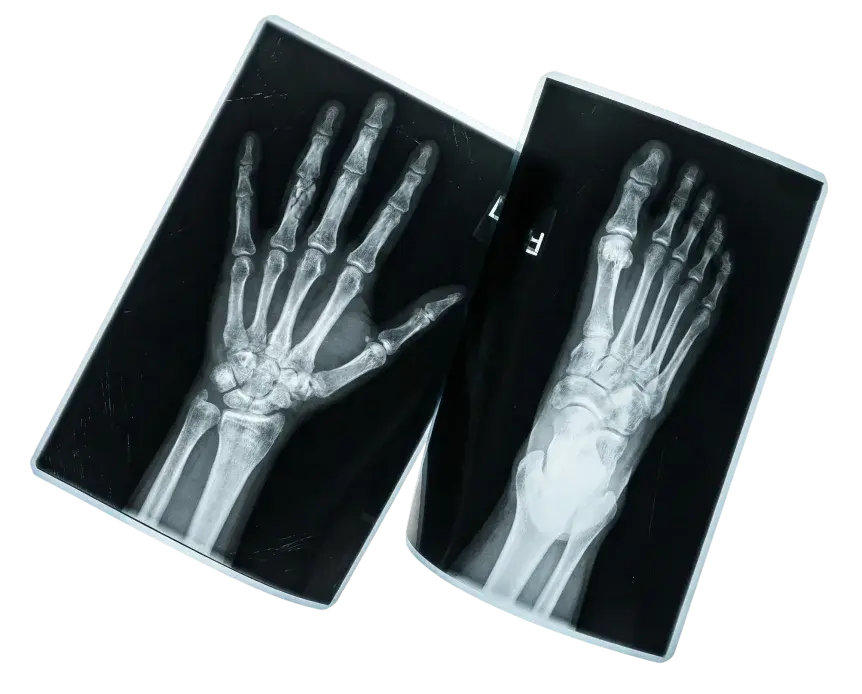

Мы предлагаем комплексное лечение заболеваний и травм кисти, руки и запястья

Хирургия кисти

Хирургия кисти: уверенность в каждом прикосновении

Главная особенность хирургии кисти — ювелирная точность. В этой зоне все структуры расположены очень компактно: нервы, сосуды, сухожилия и мелкие суставы работают в тесной связке.

Повреждение одной структуры неизбежно влечёт за собой нарушение функции всей конечности. Именно поэтому операции на кисти требуют от хирурга не только глубоких знаний анатомии, но и виртуозного владения техникой.